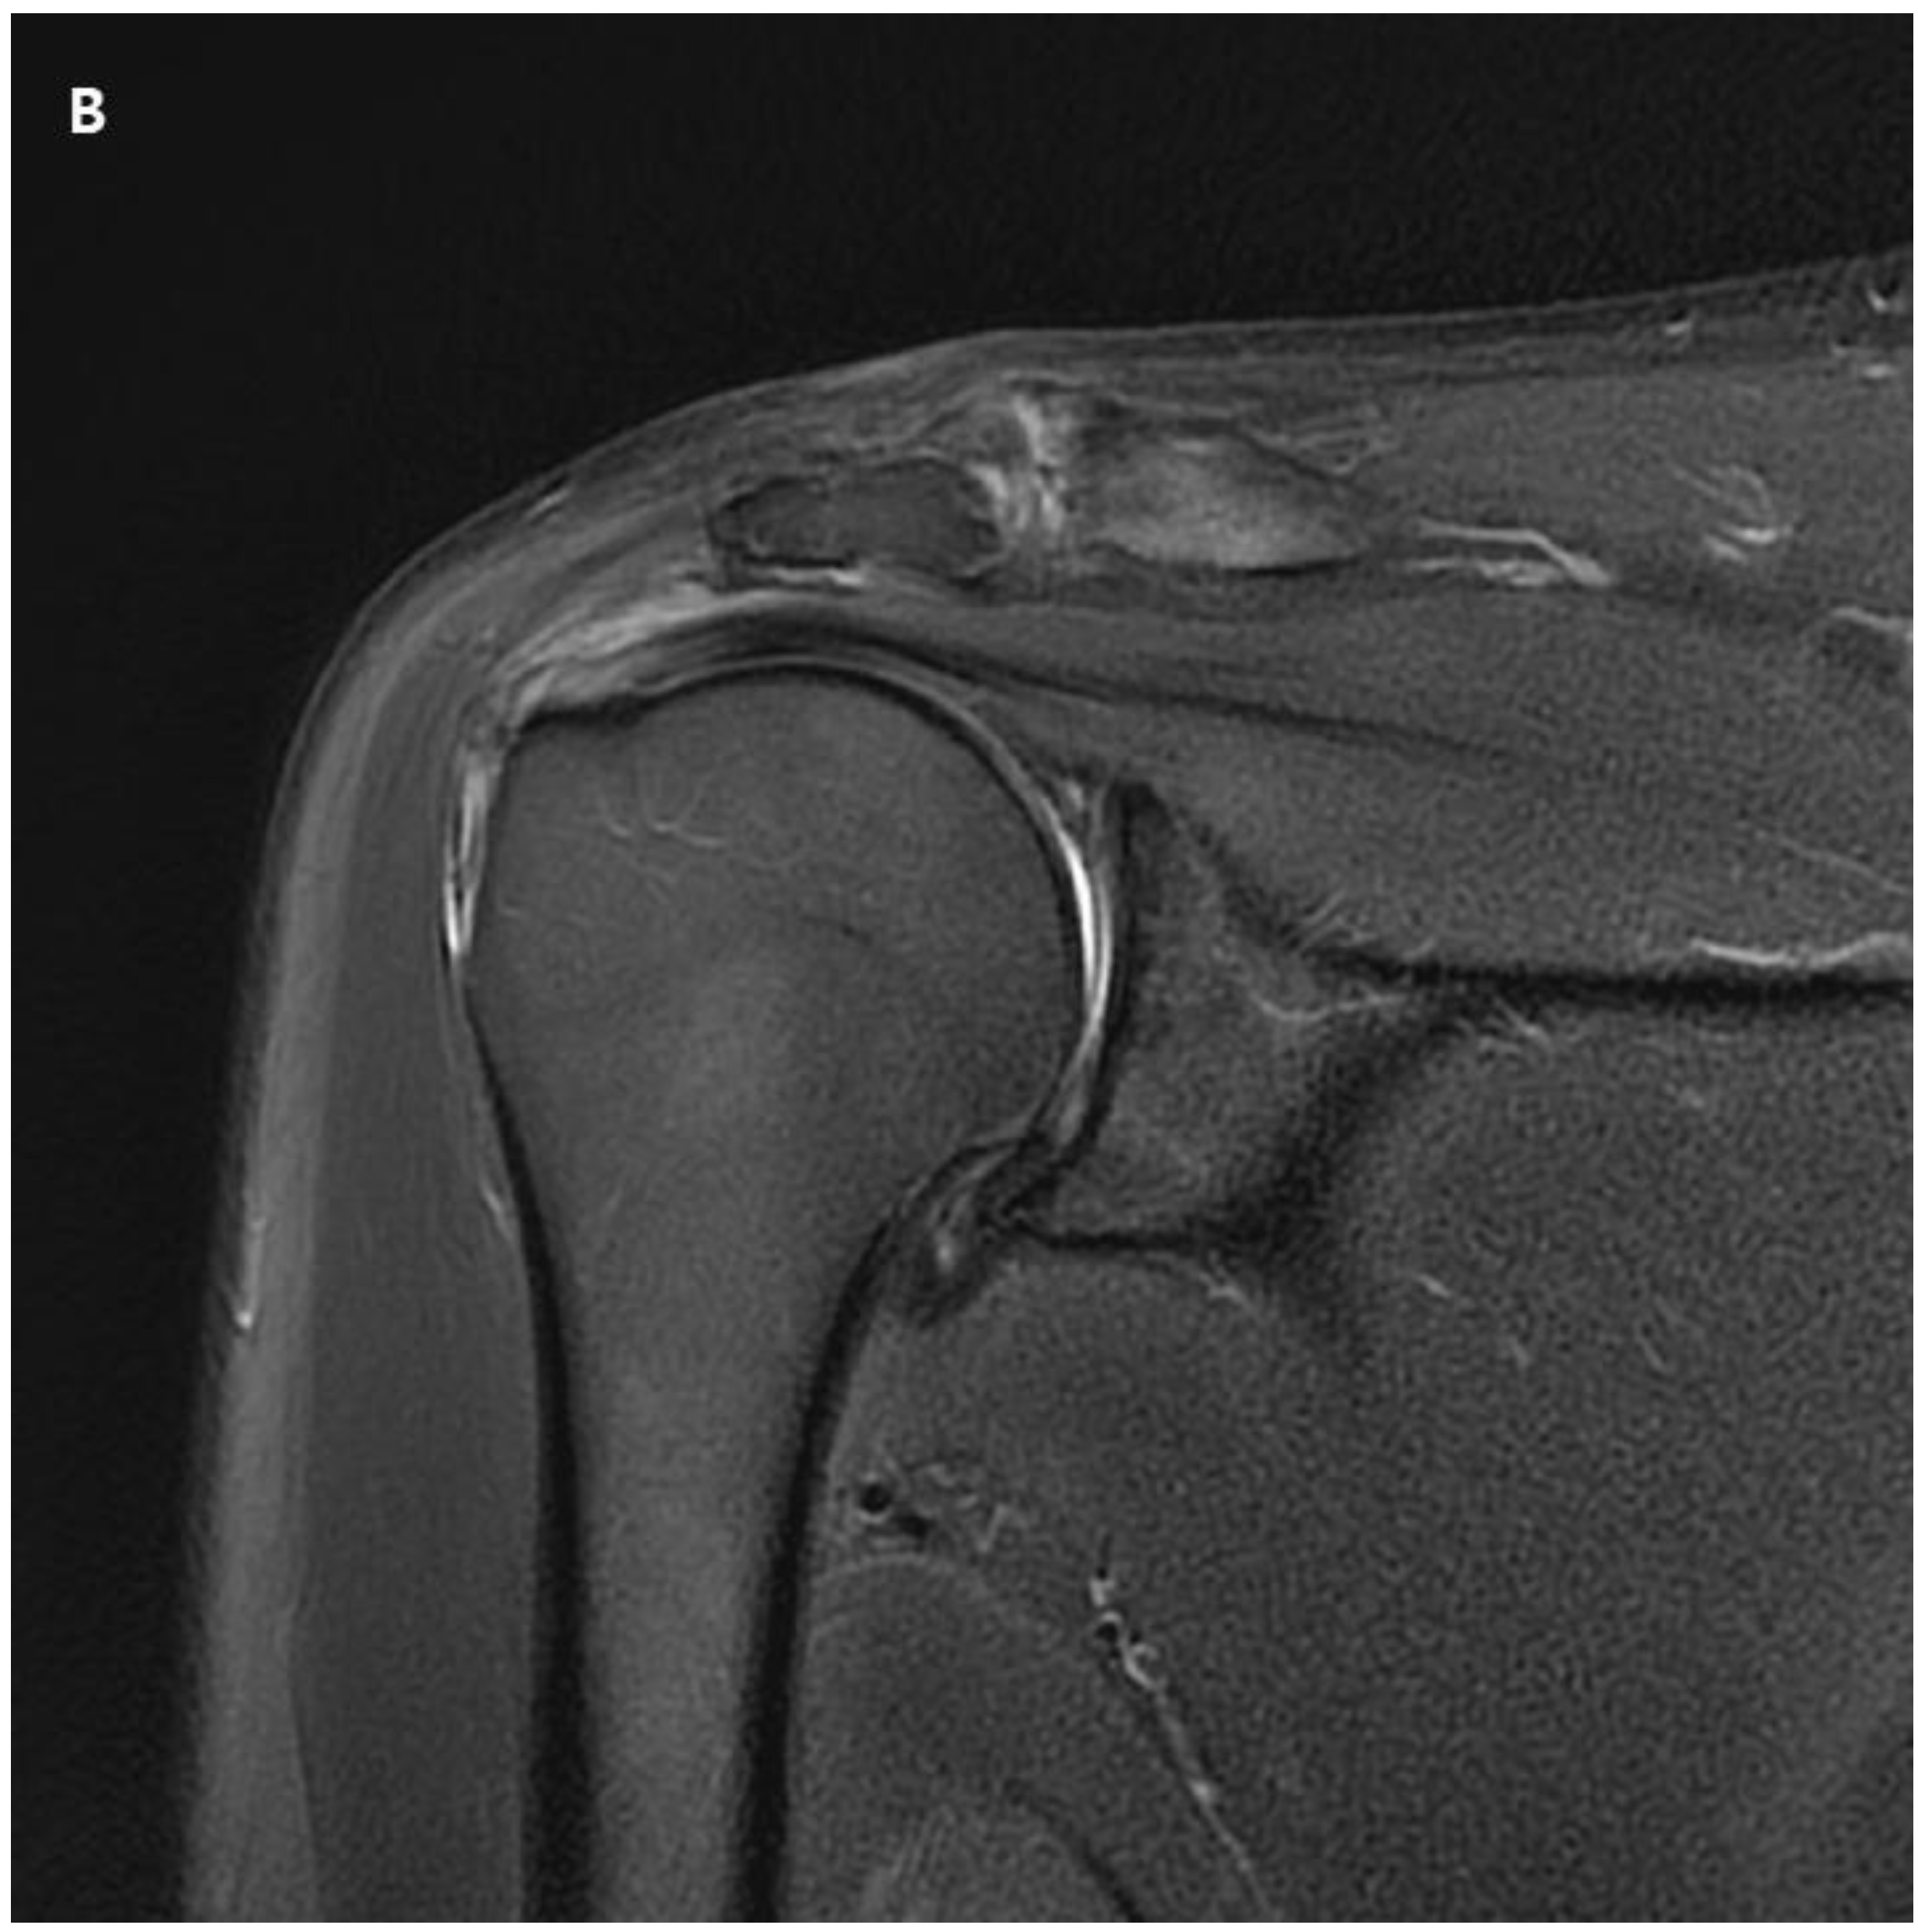

The patient returned to the hospital 21 months after the ACR with right shoulder pain. Plain shoulder anteroposterior radiography and MRI showed a subchondral cyst and a high bone marrow signal on the epiphysis of the superomedial area of the humeral head on T2-weighted images, suggesting avascular osteonecrosis of Cruess stage II (Fig. 4). The patient denied any traumatic injury, radiotherapy, exacerbation of chronic hepatitis, alcohol consumption, or use of other medications. The patient received six intra-articular injections of glucocorticoids during the 15 months of open follow-up at another institution. It is unclear whether the six intra-articular injections were corticosteroids. At 3-years postoperatively, his VAS score was 3, ASES score was 63, and CMS score was 59, indicating increased discomfort. As the patient found the discomfort tolerable in terms of both work capacity and activities of daily living, we decided to maintain the current status and continue observation until osteonecrosis progressed (Fig. 5.)

Figure 4. A. Postoperative plain radiograph obtained at 21 months post-ACR. B. Oblique coronal T1 fat-suppressed MRI. C. Oblique coronal T2 fat-suppressed MRI shows osteolytic changes in the superomedial humeral head. MRI shows cystic changes in the epiphyseal area, but articular congruity remains preserved.